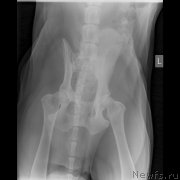

Второй ветеринар сделал ренген, где ничего не видно кроме начинающегося артроза.Опасения что слопал кость-отмели.

Сделали цифровой рентген в соседнем городе(Темиртау).Сейчас постараюсь его выставить.На мой взгляд не очень удачный.завтра наверное переделаем.

По клинической картине и по снимкам - спондилёз поясничного отдела позвоночника. Лечение: первые сутки дексаметазон 4 мг 3 раза /день или преднизолон, можно внутримышечно, и римадил 100мг 3 раза в день.